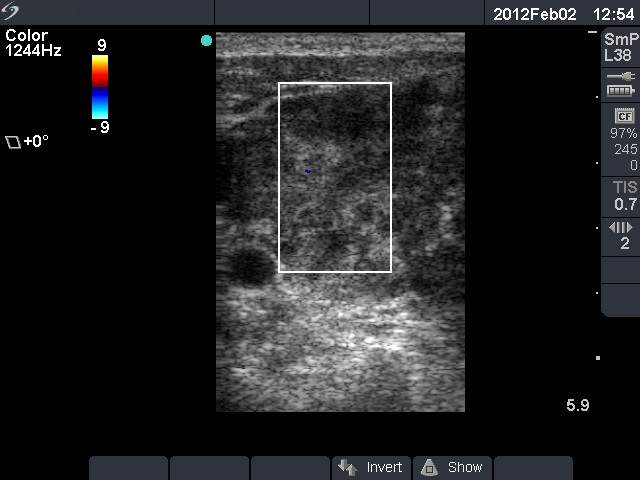

Ultrasonography: Both lobes were deeply hypoechoic. There was a large lymph node just lateral to the left thyroid lobe. The node had a central scar and presented echonormal discrete fields as well. It is worth noting that the left thyroid lobe was more inhomogeneous compared to the other thyroid lobe. This inhomogeneity made the appearance of the left lobe close to the tumorous lymph node.

On the ultrasound presentation, it was not evident that the thyroid also has malignant lesion, but the histopathology disclosed that the lymphoma was present even within the thyroid.